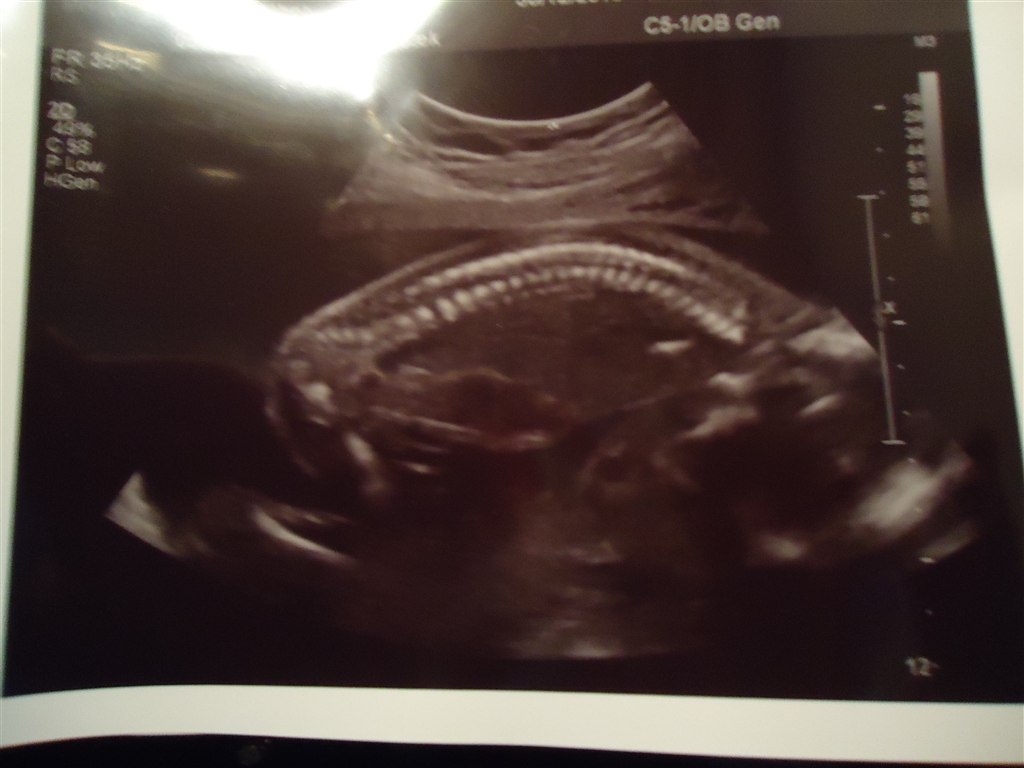

og så var vi til MD-scanning i torsdags, og hun var helt perfekt vores lille pige, 20 cm og 367 gram